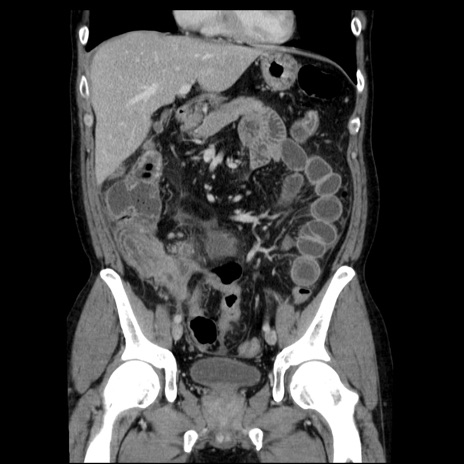

症例29(冠状断像)

【症例】40歳代男性

【現病歴】2日前から胃痛あり。徐々に周期的な激痛に変化した。本日になっても激痛があるため受診。

【身体所見】意識清明、BT 38-39℃台あり、腹部:膨満、やや硬、右下腹部に圧痛あり。

【データ】WBC 8500、CRP 23.26